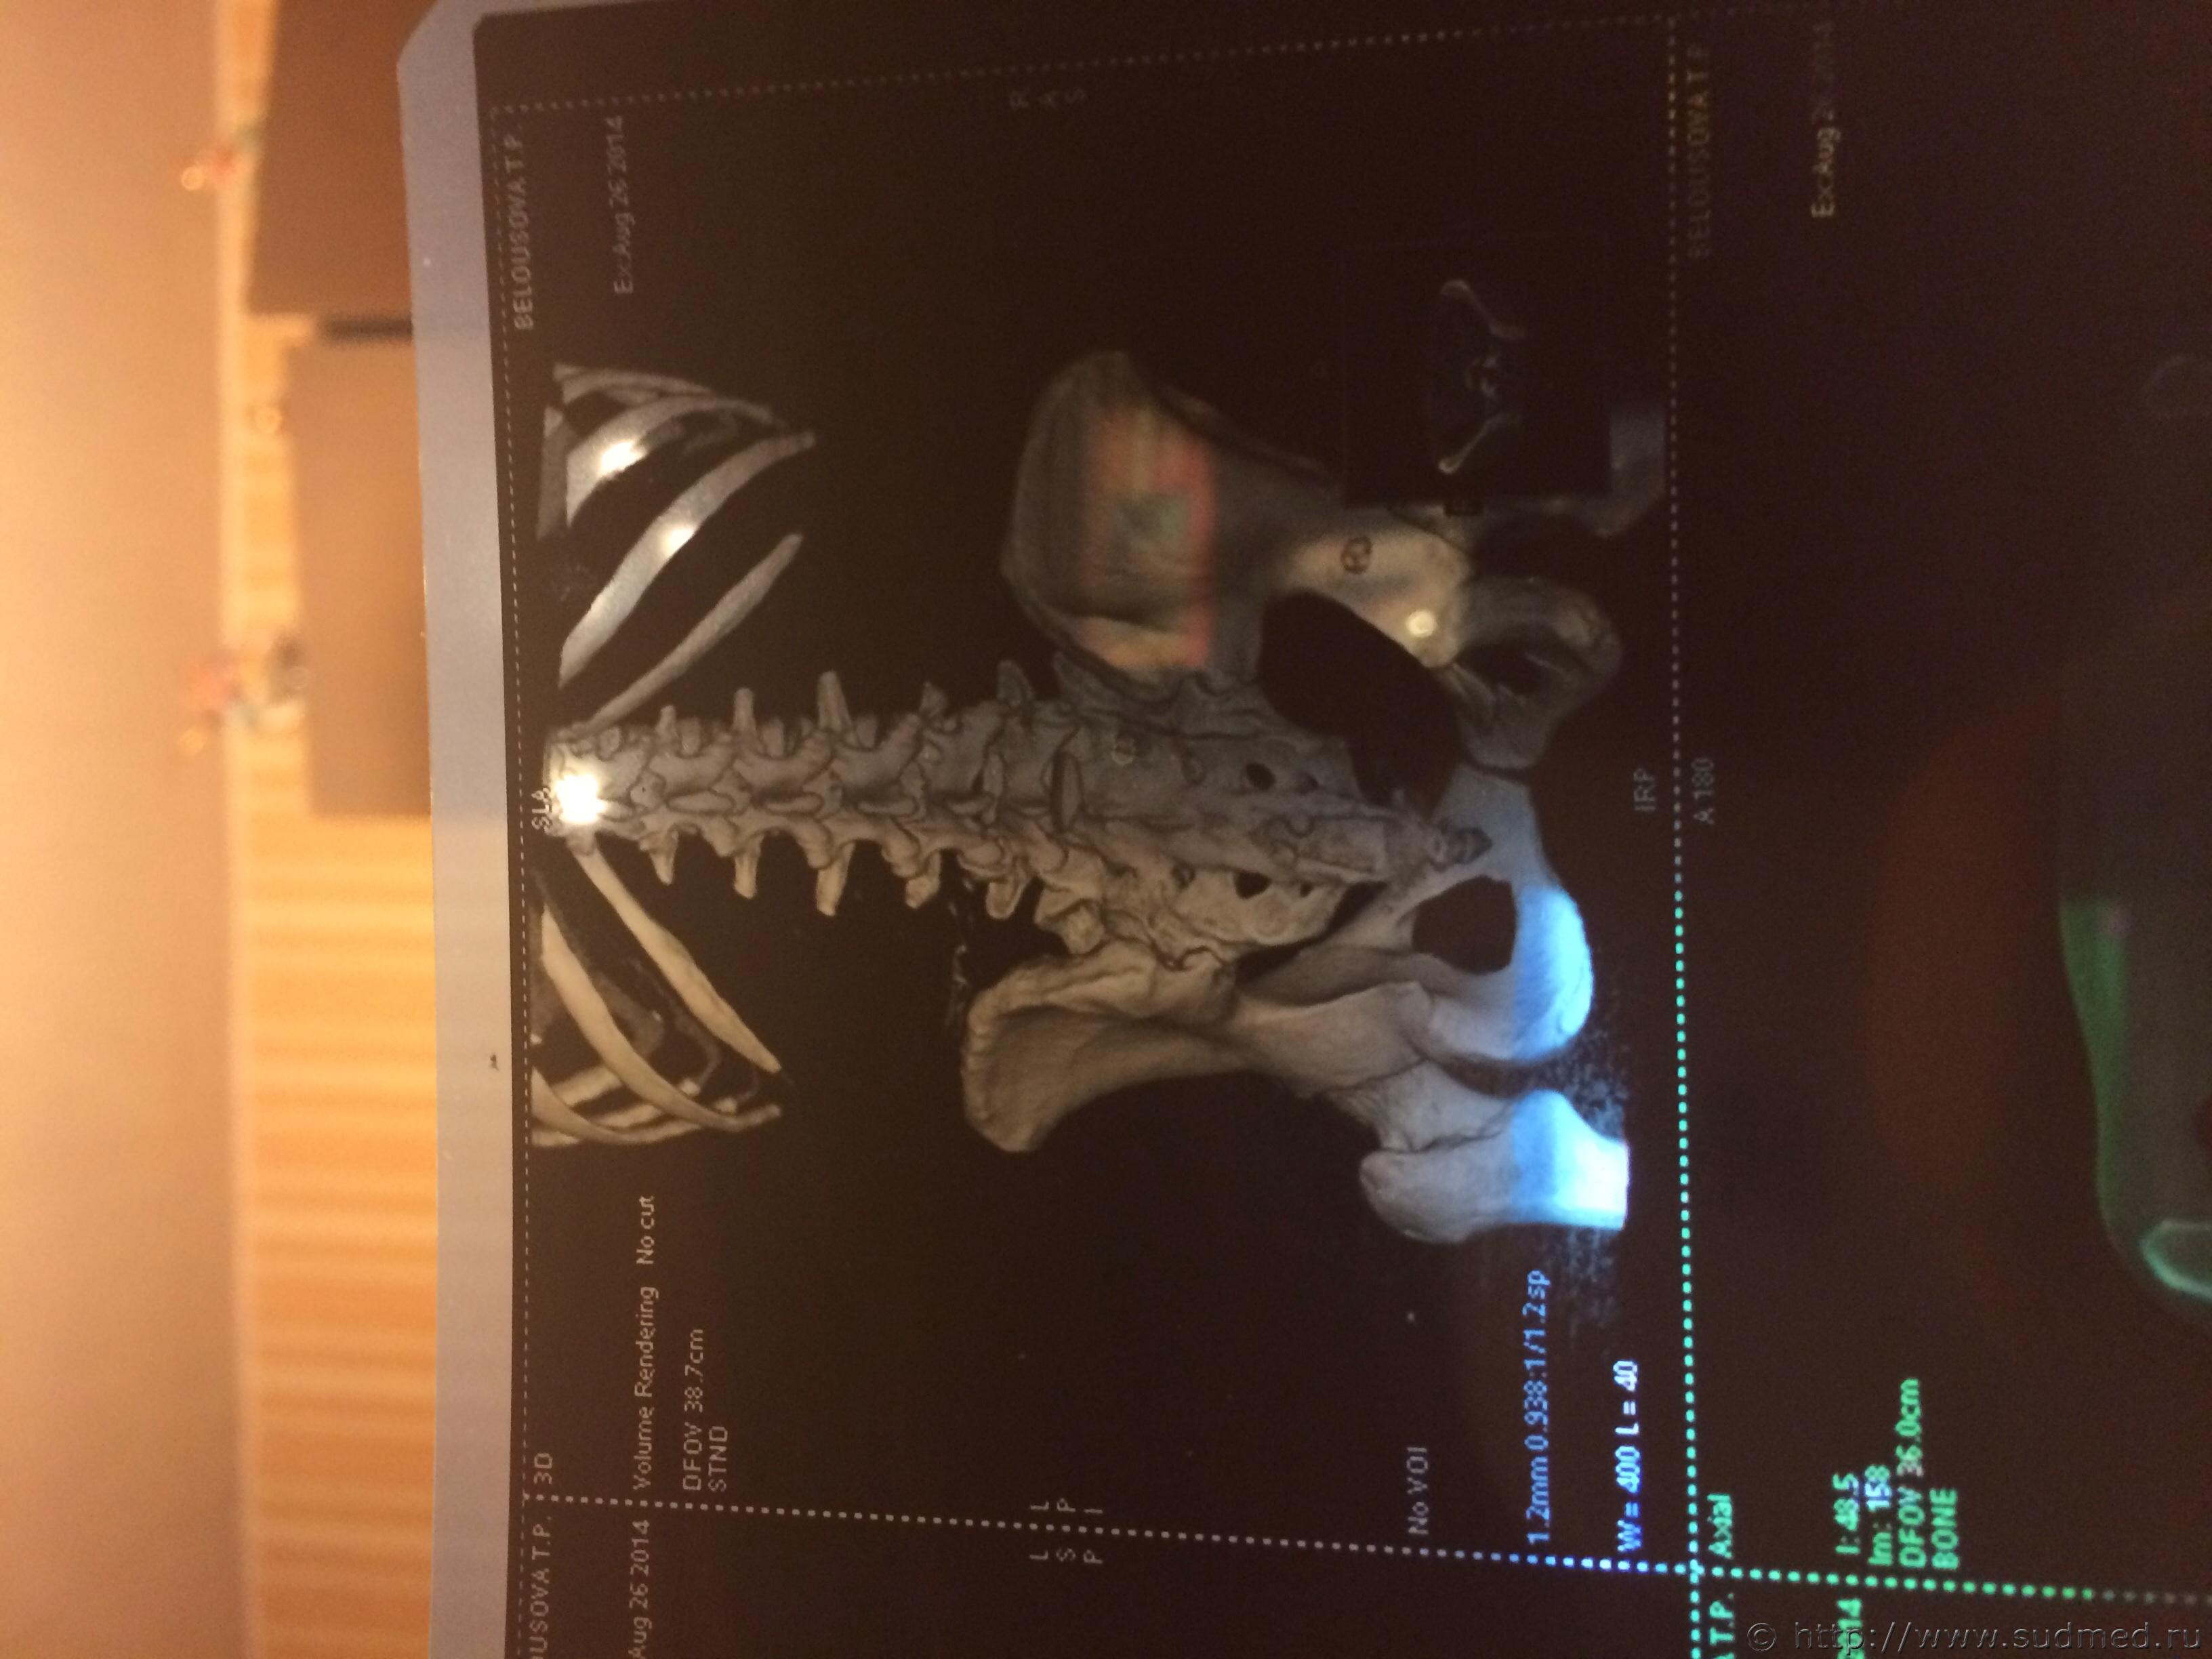

Спасибо! У меня результаты КТ, ошиблась)

КТ

Как мне видится - вертикальный перелом крестца. Тяжкий вред.

Впрочем, оставляю небольшую вероятность, что я не видел все сканы, да и качество их здесь, разумеется, хуже, чем изображение на пленке или на экране компьютера у врача, работающего на томографе.